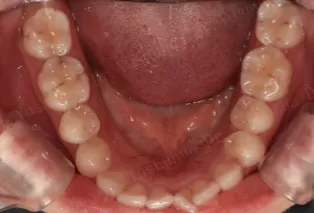

Photos intra-orales